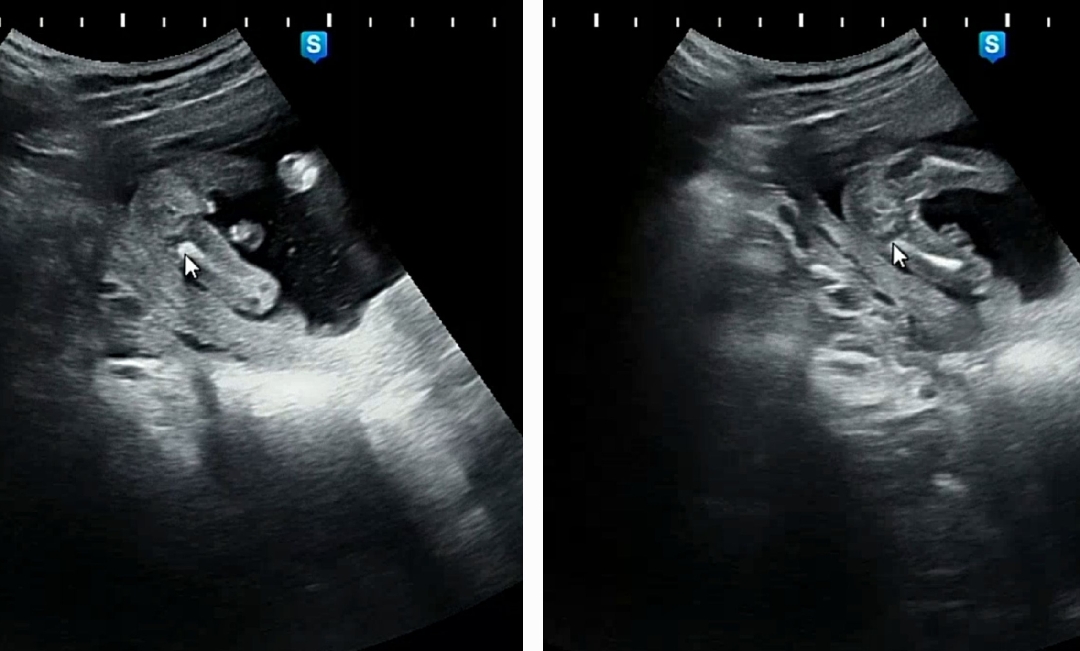

오늘 16주 초음파 보고왔어요~ 의사분께서는 70프로 확률로 딸같다고 하시는데 앞사진에서 보이는거 같기도 하구😂 너무 애매하네요ㅠㅠ 참견 부탁드려용~!

선생님이 딸이라고하면 보통 맞아요 ㅎㅎ

아무것도 안보이는거 같은데요? 저도 엊그제 보고왔는데.. 누가봐도 아들은 그냥 ㅌ자로 똭 튀어나와있드라구요..